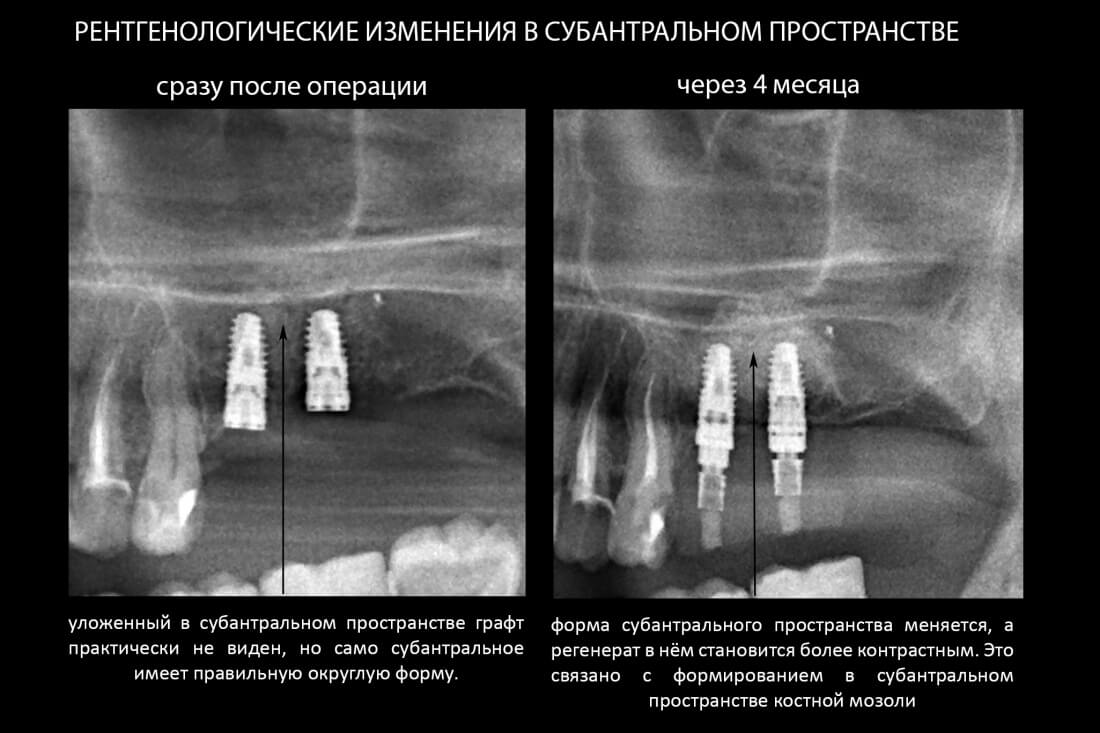

Прошло около четырех месяцев. Мы запланировали следующий этап лечения, формирование десневой манжеты (ФДМ).

Вот клиническая картина через 4 месяца после ранее проведенной имплантации с остеопластикой:

И КЛКТ показала нам, что с имплантатами и окружающей костью всё зашибись. Через 12 лет после операции, отсутствия наблюдения, пофигизма в замене временных коронок! Нужны ли тебе еще какие-нибудь доводы в пользу долгосрочной эффективности метода?

Серия контрольных снимков на этапах: